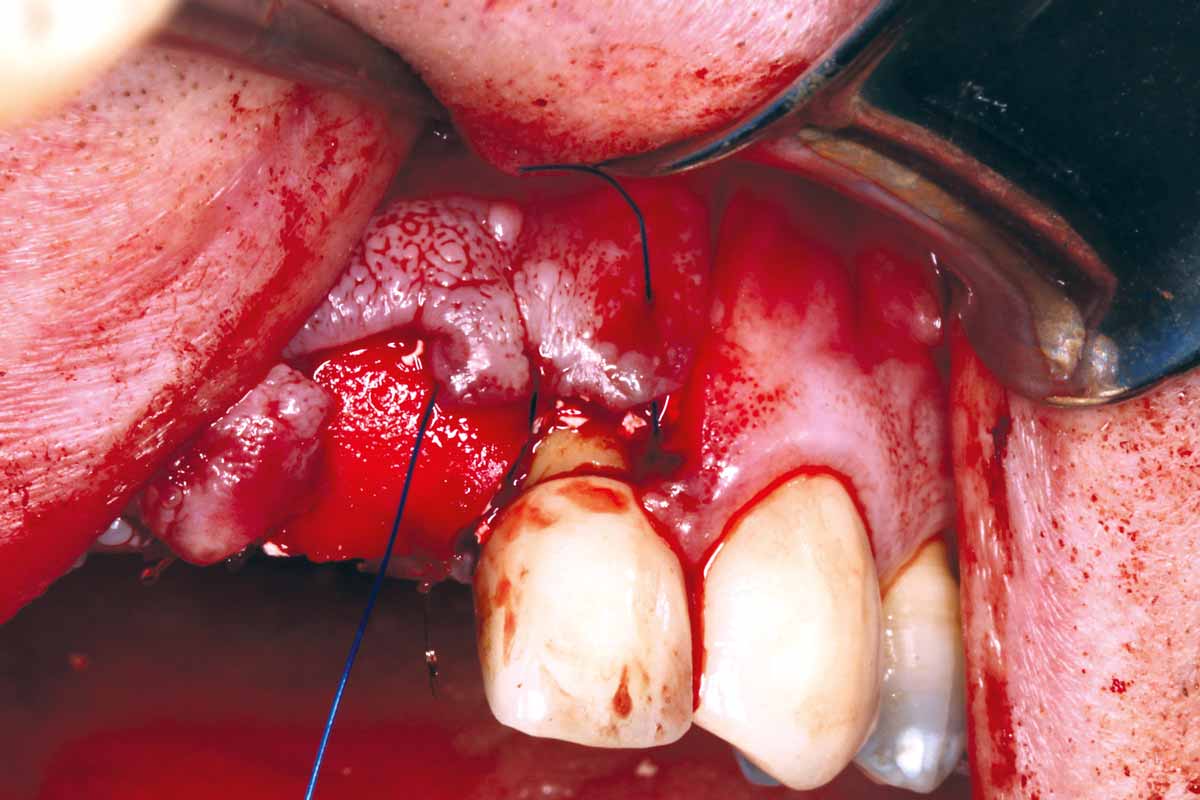

9/27 - GBR with autologous bone chips covered with small particles cerabone® and two mucoderm® used as a barrier membrane

GBR and soft tissue augmentation with cerabone® and mucoderm® - H. Maghaireh & V. Ivancheva